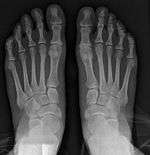

Syndesmosis procedure addresses specifically the two fundamental problems of metatarsus primus varus deformity that gives rise to the bunion deformity. They are leaning and instability of the first metatarsal bone . Syndesmosis procedure uprights the leaning first metatarsal bone with strong binding sutures between it and the second metatarsal bone (Fig. 2) and then also stabilizes it uniquely by creating a fibrous connecting bridge between these two bones (Fig. 3,4). First metatarsal bone can be readily realigned is because by definition of the metatarsus primus varus deformity its first metatarsal is abnormally loose and mobile.